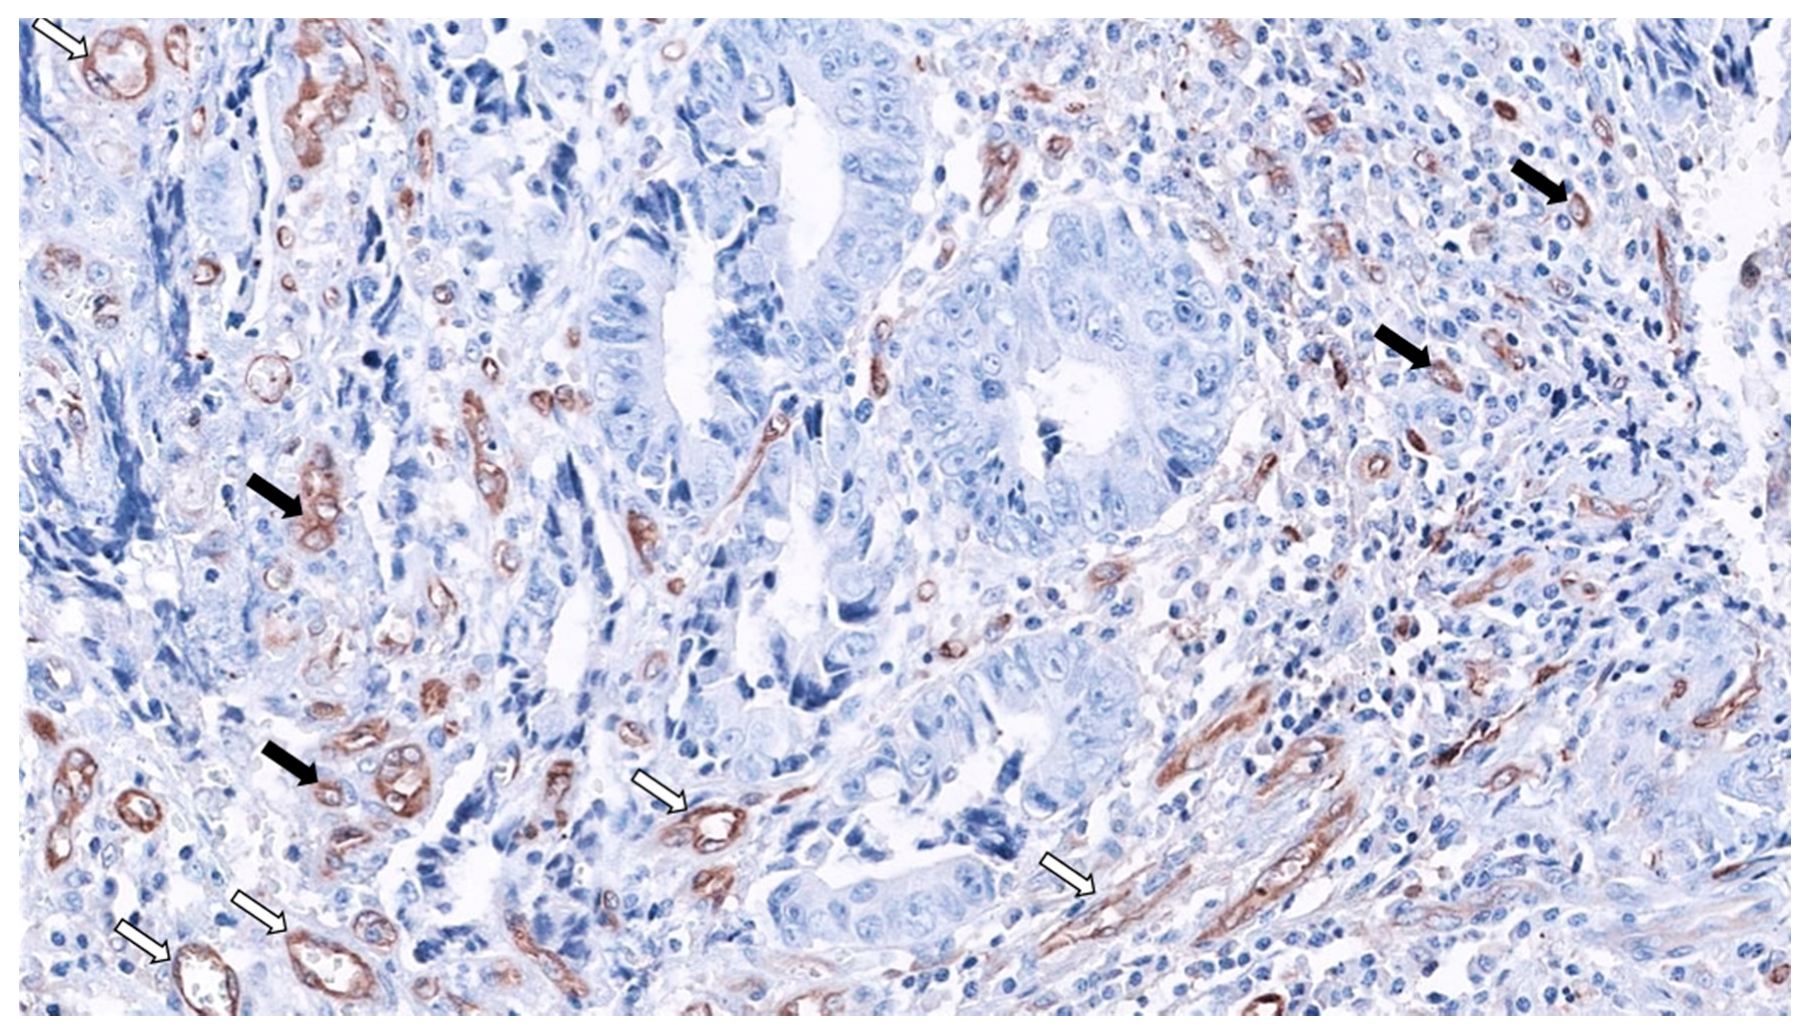

Figure 3.

Fascin1 expression in SAC-staining tumor-budding cells (black arrows) and abundant surrounding microvessels (white arrows) 20× original magnification. (Source: Authors).

MVD was significantly higher in SACs, and, surprisingly, serrated morphology was the only significant predictor of MVD in CRC after multivariate analysis. Finally, regarding the mechanism of HIF-1α stabilization, HIF-1α expression was characteristic of well-vascularized tumor in SACs, suggesting a hypoxia-independent mechanism. Besides, in this study, neither BRAF nor KRAS mutation status was associated with HIF-1α and VEGF expressions, nor with HIF-1α stabilization in CC or SACs. Even more, the great majority of SACs carrying wild-type alleles for KRAS and BRAF (81%) were HIF-1α proficient, pointing out to other mechanisms for HIF-1α stabilization in SACs [25]. Figure 3 shows the abundance of SAC-associated MVD using fascin1 immunohistochemistry.

Fascin1 emerged as an immunohistochemical marker for SAC diagnosis, as the positive expression of fascin1 was observed in 88.6% of SACs and in 14.3% of CCs (88.6% sensitivity, 85.7% specificity) [12]. Intriguingly, Tao et al. had previously observed that β-catenin is associated with the actin-bundling protein fascin in a non-cadherin complex. In fact, these authors observed that fascin1 and E-cadherin use a similar binding site within beta-catenin and that fascin and beta-catenin co-localize at cell–cell boundaries and dynamic cell-leading edges of epithelial and endothelial cells [111], thus giving an explanation of why β-catenin was not observed in the nuclear location in SACs. Fascin1 protein localizes to the core actin bundles forming spikes and filopodia at the leading edge of migratory cells, increasing migration in several cell types [112] and therefore, it has been associated with adverse prognosis in CRC [113]. These facts can partly explain the higher incidence of adverse prognostic histologic factors at the invasive front of SAC (HG-TB and weak peritumoral lymphocytic infiltration (PLI)) and the worse outcomes observed in SACs [18]. Additionally, fascin1 expression is associated with shorter survival, as has been reported previously in CRC [114], thus supporting earlier observations showing that SAC fares worse than CC [113]. Induced expression of fascin1 in colorectal cancer cells increased migration and invasion in cell cultures and caused cell dissemination and metastasis [115]. Figure 3 shows the expression of fascin1 in both blood vessels and SAC cells at the invasive front, creating tumor budding.